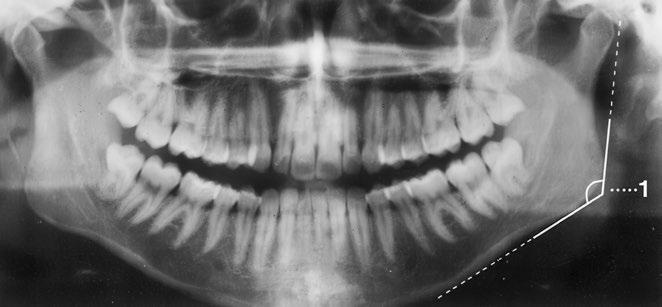

Ortopantomogram čelistí a obličejového skeletu

Zobrazené úseky horní a dolní čelisti i obličejového skeletu jsou tvarem a velikostí normální Mineralizace a kostní struktura jsou rovněž normální Hladké a ostré ohraničení okrajů kortikalis bez patologického přerušení kontur

Nenápadná kontura nervového kanálu v alveolární kosti

Náležité zobrazení obou čelistních kloubů s normálně širokou kloubní štěrbinou

Chrup sanován, počet, postavení, tvar a struktura zubů jsou normální Kořeny sahají normálně daleko do alveolární kosti bez známek rozšíření parodontální štěrbiny

Dutiny čelistní a paranazální jsou volně provzdušněné a mají stejně jako dna orbit hladké kontury stěn

Rentgenkontrastní cizí tělesa nejsou, měkké tkáně bez otoku

Závěr

Normální zobrazení horní a dolní čelisti a zachyceného obličejového skeletu

Důležité údaje (1) Čelistní úhel 110–140°

Stav chrupu: 28 zubů a 4 zuby moudrosti